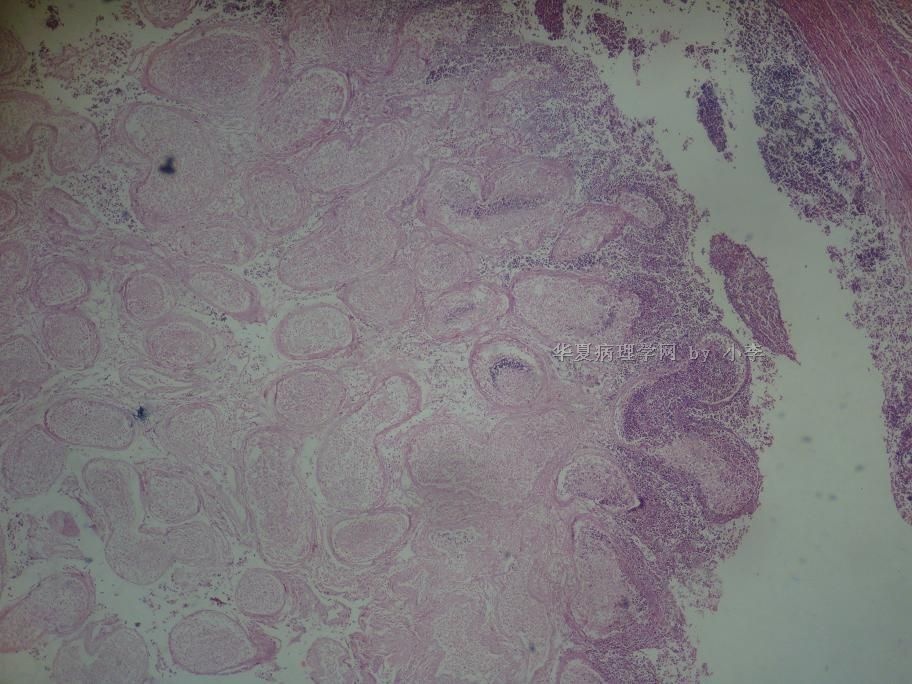

睾丸炎?

• 睾丸炎?图3

图3

首先考虑精子肉芽肿

慢性肉芽肿性炎

肉芽肿性睾丸炎

精子肉芽肿